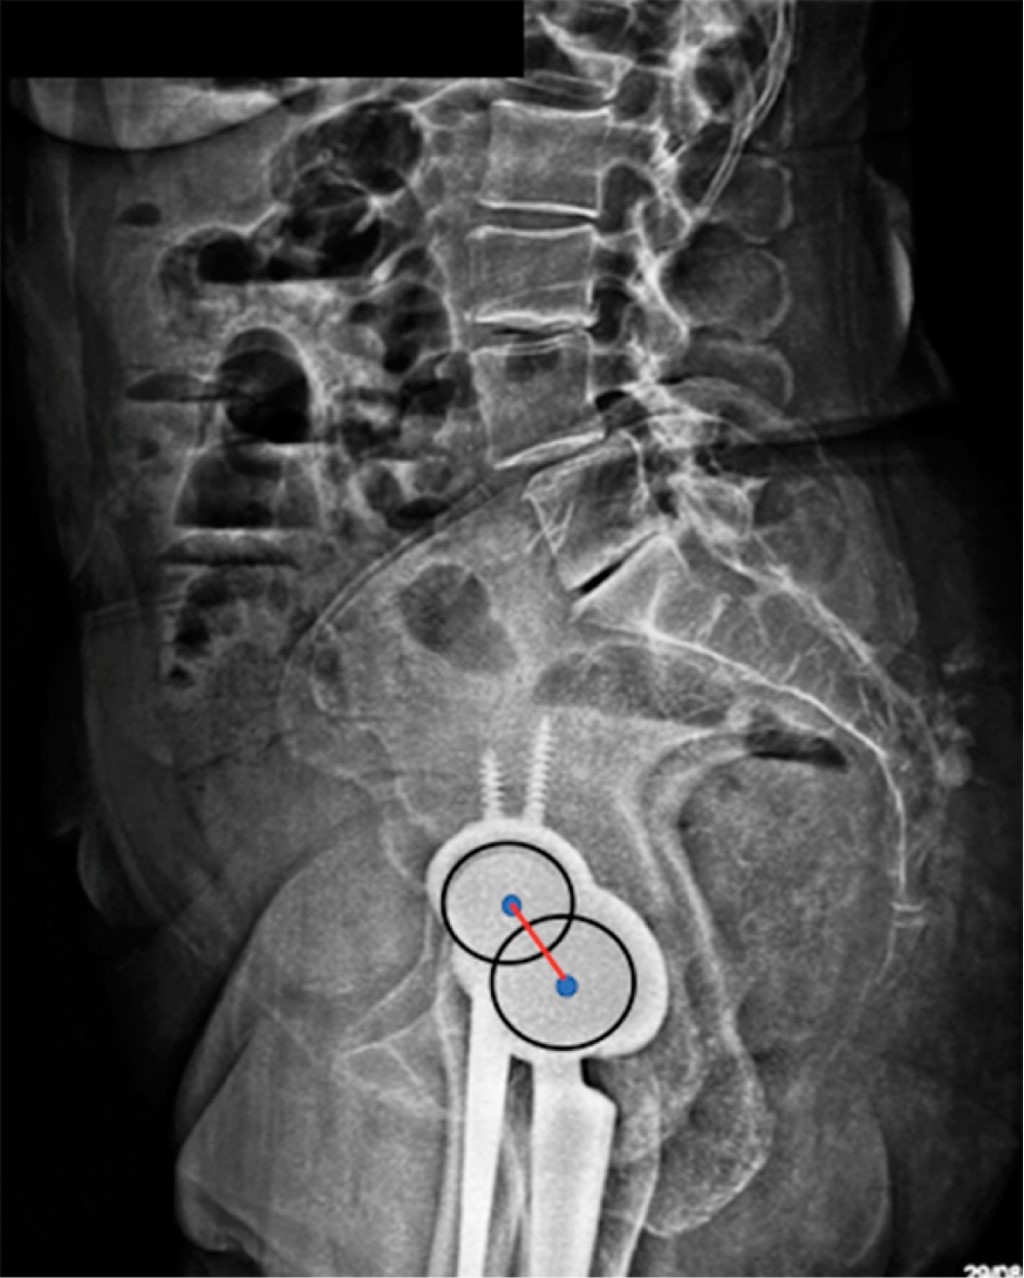

Es oportuno abrir aquí un paréntesis para definir qué es el "eje bicoxofemoral". Debido a que en una radiografía lateral es muy difícil hacer coincidir los centros de rotación de ambas cabezas femorales, se utiliza el concepto de "eje bicoxofemoral". Este eje se localiza en la parte media de una línea trazada entre los centros de rotación de ambas cabezas femorales en una radiografía lateral espino-pélvica (Figura 17).

Figura 17